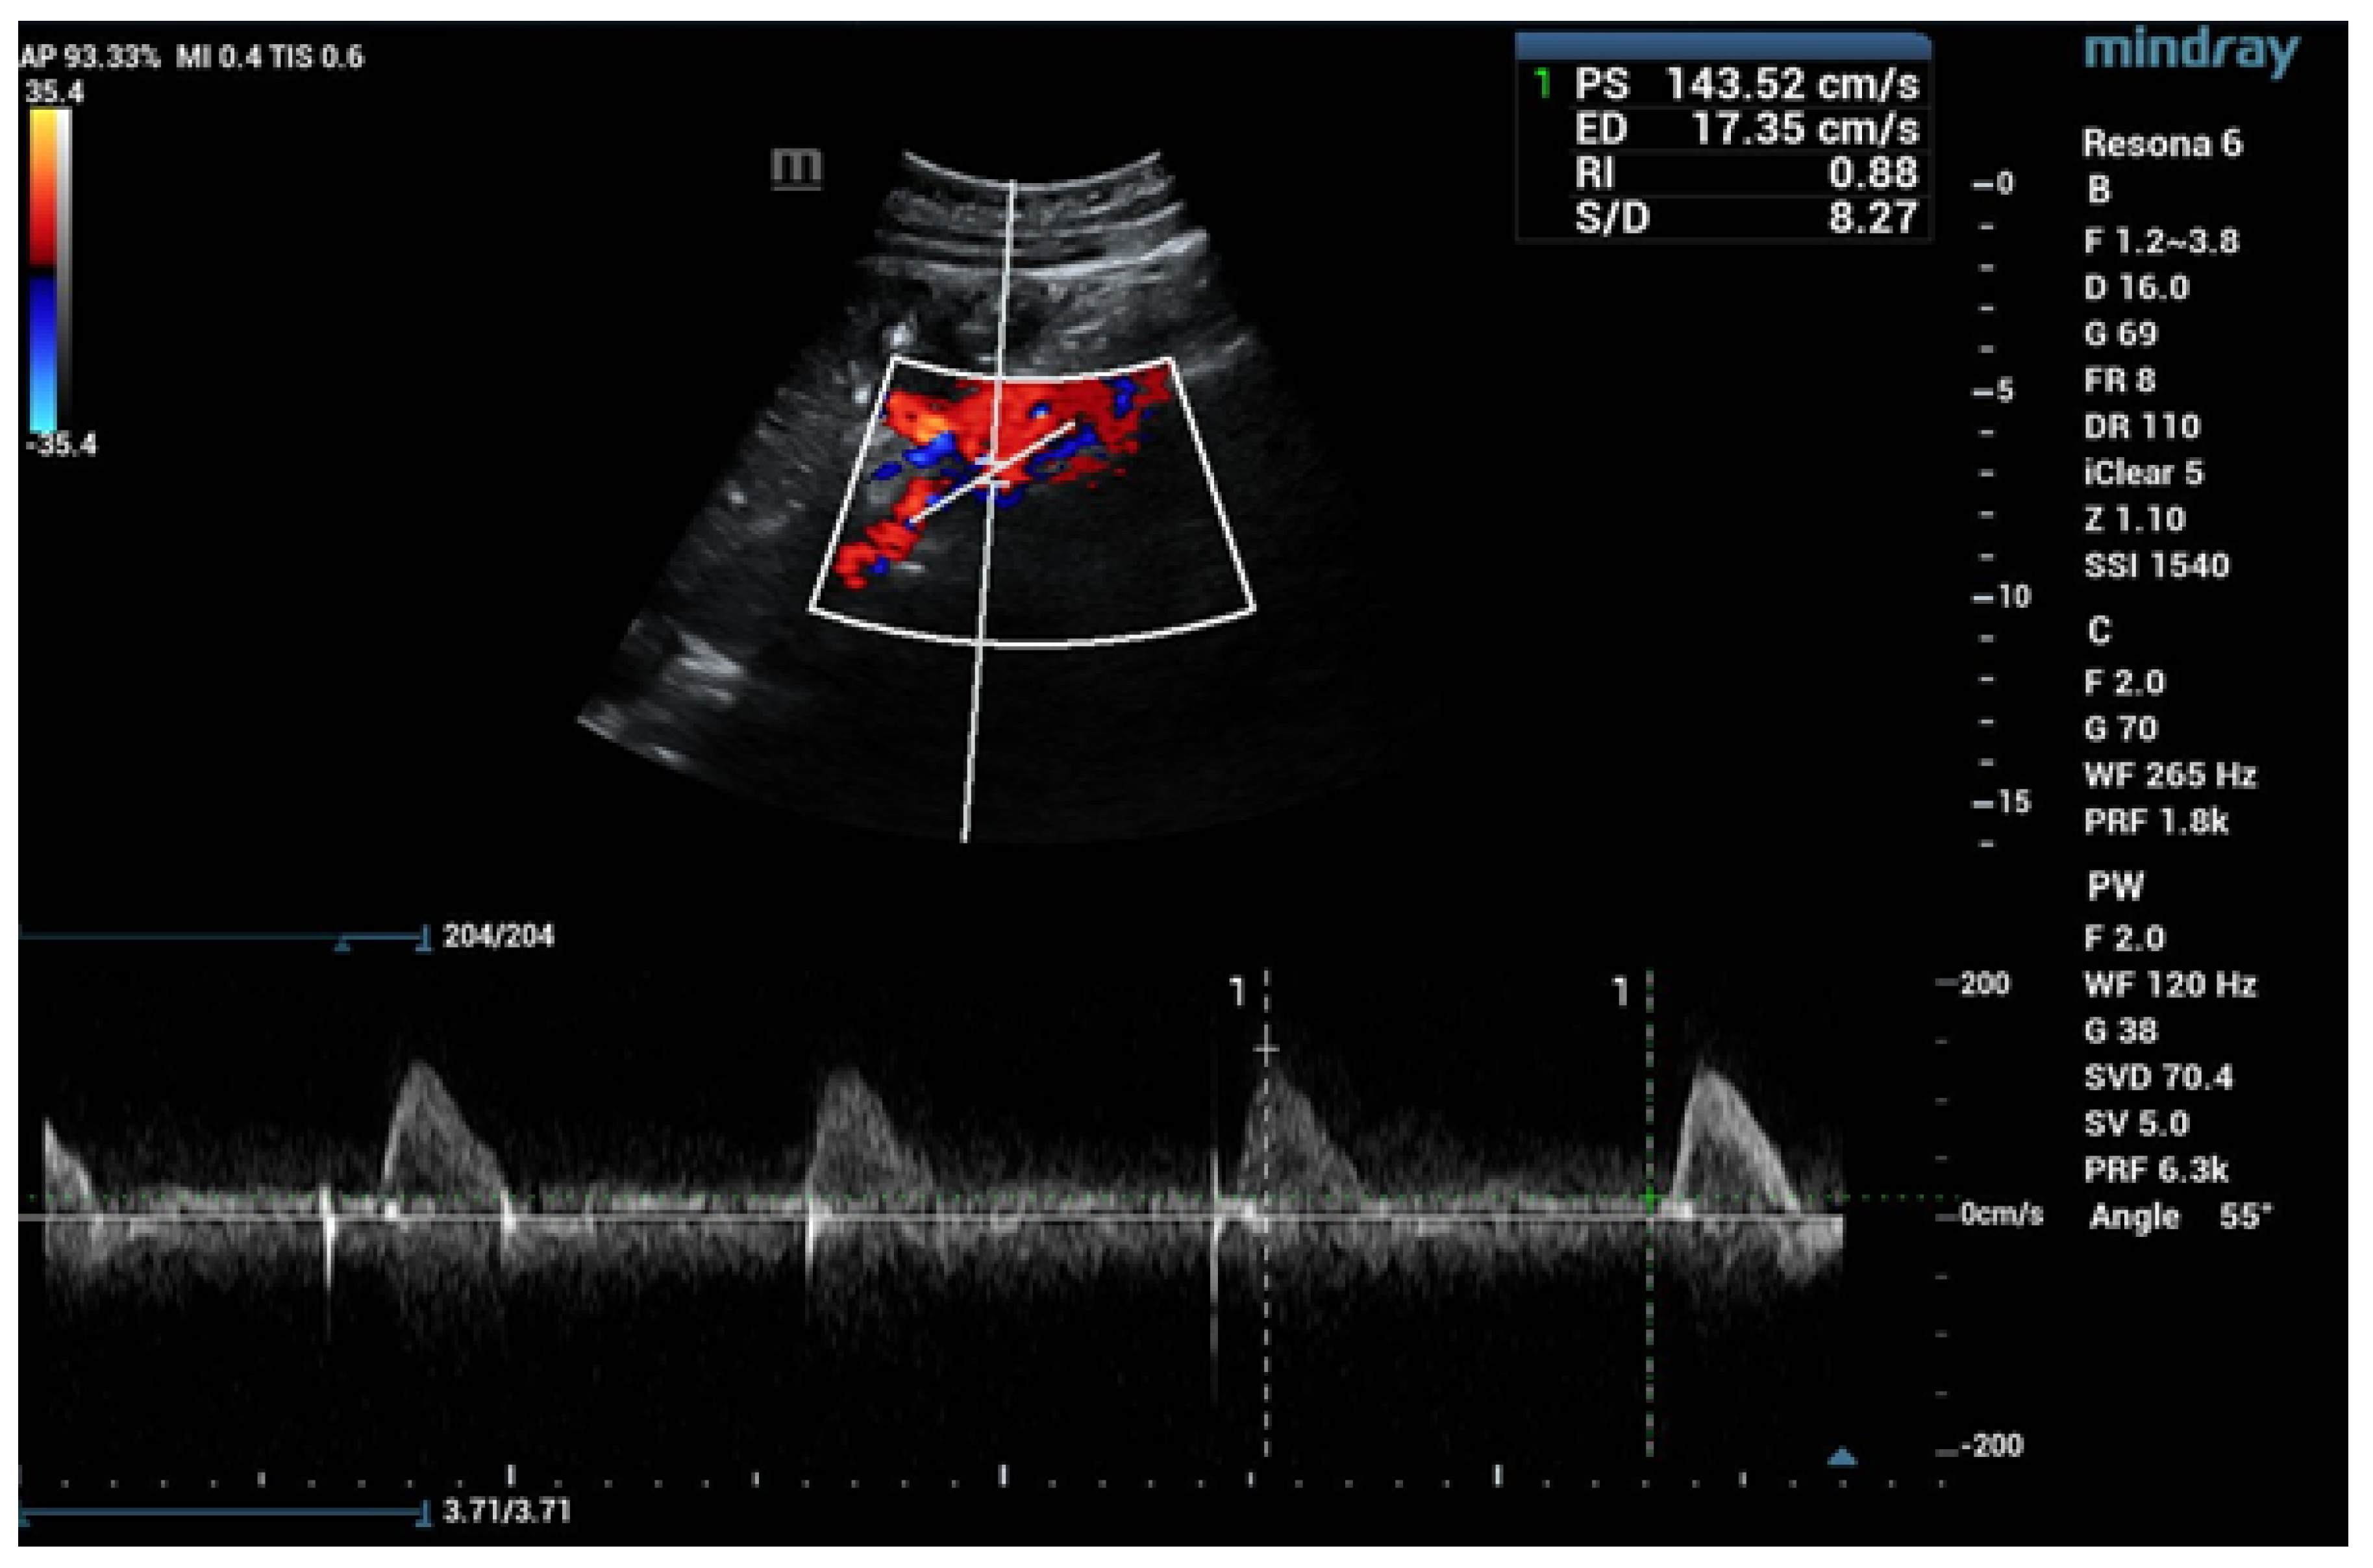

6.1. Ultrasound

- Drelich-Zbroja, A. Polish Society of Ultrasonography Standards—Update: Ultrasound Examination of Renal Arteries. J. Ultrason. 2014, 14, 297–305. [Google Scholar] [CrossRef]

- Stryczyński, Ł. Doppler ultrasound of renal arteries. Arter. Hypertens. Pract. 2022, 8, 186–199. [Google Scholar]

| Normal Value | Parameter |

|---|---|

| 100 cm/s * | PSV (peak systolic velocity) in artery trunk |

| 0.8–1.0 | RAR (renal aortic ratio) in artery trunk |

| ≤70 ms | AT (acceleration time) in intrarenal branches |

| 0.5–0.8 | RI (resistance index) in intrarenal branches |

| 0.78–1.33 | PI (pulsatility index) in intrarenal branches |

| >3 m/s2 | AI (acceleration index) in intrarenal branches |